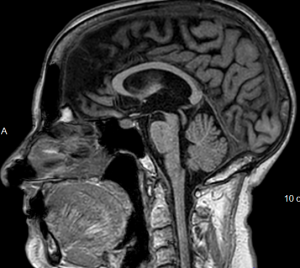

Parkinson plus é um conjunto de doenças neurodegenerativos que se caracterizam por sintomas semelhantes aos da doença de Parkinson, por isso também são chamadas de Parkinson atípico ou Parkinson Like. Esses sintomas incluem tremor, rigidez muscular, dificuldade de movimento, dificuldade de equilíbrio e coordenação. No entanto, os pacientes com esses transtornos geralmente também apresentam outros sintomas que não estão presentes na doença de Parkinson, como demência de rápida evolução, transtornos da motricidade ocular e problemas com a fala.

Os transtornos neurodegenerativos que são classificados como “Parkinson plus” incluem a atrofia de múltiplos sistemas, a demência por corpos de Lewy, a degeneração cortico-basal e a paralisia supranuclear progressiva (PSP).

A demência por corpos de Lewy é uma condição semelhante que se caracterizam por aglomerados anormais de proteínas no córtex cerebral, no interior do mesencéfalo e no tronco cerebral. Esta demência é caracterizada pelo rápido declínio cognitivo com comprometimento funcional importante associado a sintomas parkinsonianos.

A degeneração córtico-basal é uma doença rara que afeta as áreas do cérebro que controlam o movimento, a fala e a capacidade de se comunicar. Os sintomas incluem tremores, rigidez muscular, problemas de fala e dificuldade para se comunicar e escrever.

A Paralisia Supranuclear Progressiva (PSP) é outra doença neurodegenerativa que além de apresentar sintomas parkinsonianos também evolui com alteração de controle do equilíbrio e dos movimentos oculares, além de causar dificuldade para falar e deglutição.